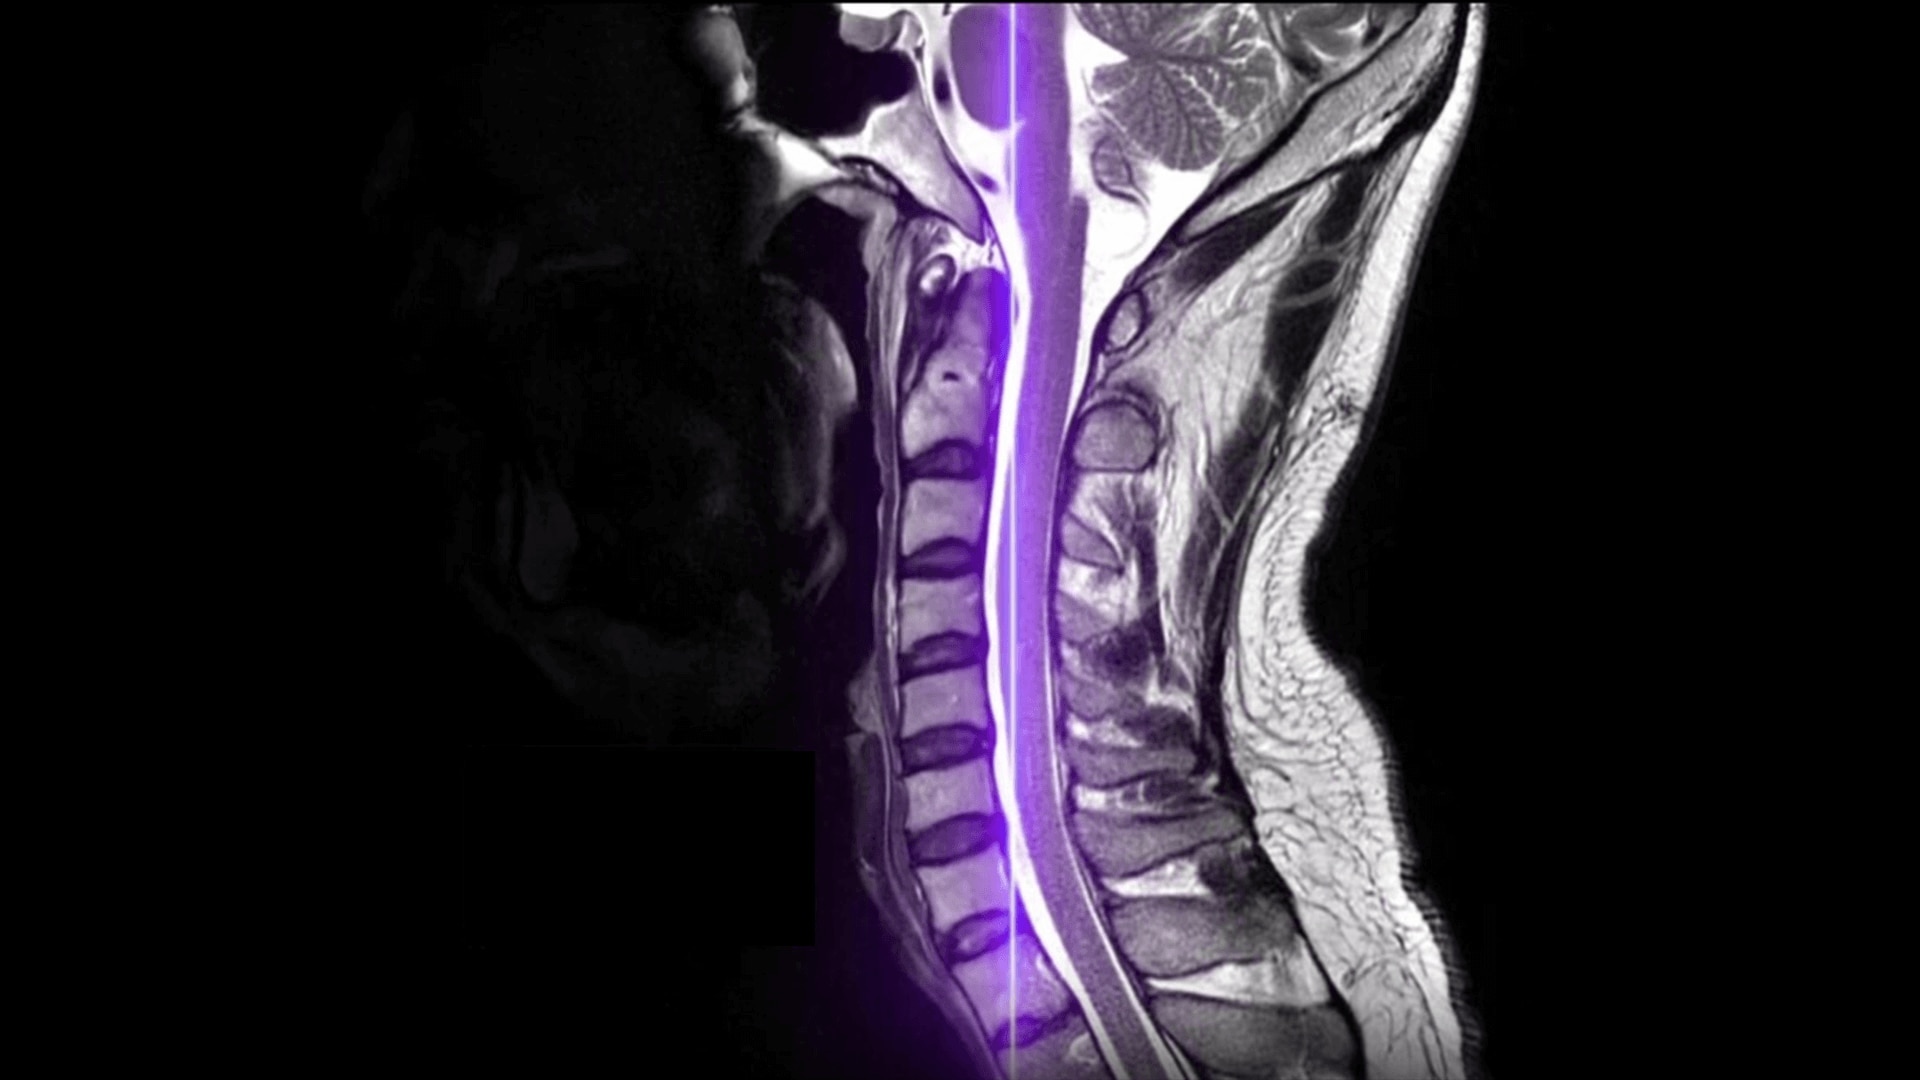

Meet our next-generation SIGNA MRI scanners & solutions

SIGNA MRI Scanners

Our 1.5T, 3T, PET/MR and 7T scanners deliver the latest in imaging innovation with AIR Recon DL, and AIR Coils.